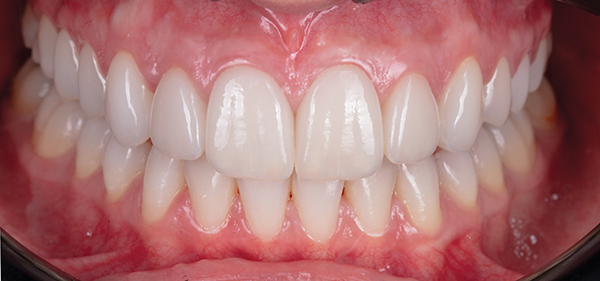

Fig 18. Intraoral view at 1-year postoperative follow-up.

Figure 18

Figure 18 and Figure 19 depict the outcome 1 year after treatment. A nightguard and professional hygiene every 3 months were recommended.